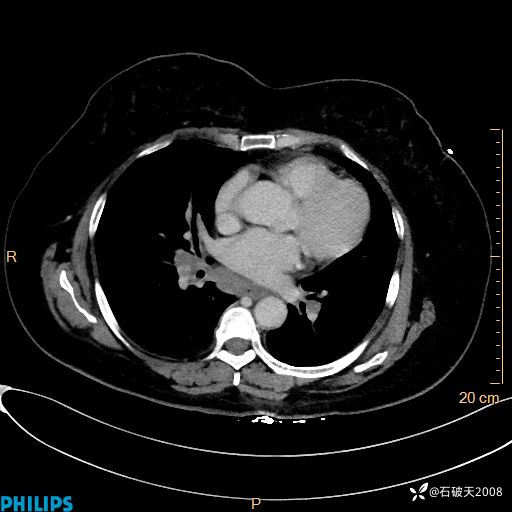

肺结节病?纵膈型肺癌?淋巴瘤?有点意思,欢迎围观

女 52岁 主 诉:咳嗽10余天,咳痰2天。

现病史:10余天前无明显诱因出现咳嗽,呈阵发性干咳,伴咽喉部发痒,无咽痛,无咳痰,无鼻塞、流涕、打喷嚏,无发热、畏寒、寒颤,无头痛、头晕,无胸闷、胸痛,无反酸、烧心,无腹痛、腹泻,无尿频、尿急,无皮疹等,在当地诊所求治,给予口服药物治疗(具体不详),病情无好转。遂在当地社区卫生服务中心开具口服药物治疗(具体不详),疗效欠佳。2天前出现咳痰,在我院门诊求治,行胸部CT提示肺部感染,建议住院,患者要求口服药物治疗,目前仍咳嗽、咳白色粘痰,白天量多,夜间自觉喉部喘鸣音,遂再次来院就诊,以“肺部感染”为诊断收入院。发病以来,神志清,精神可,饮食可,夜间睡眠差,大小便正常,近期体重无明显变化。

肺窗

纵隔窗